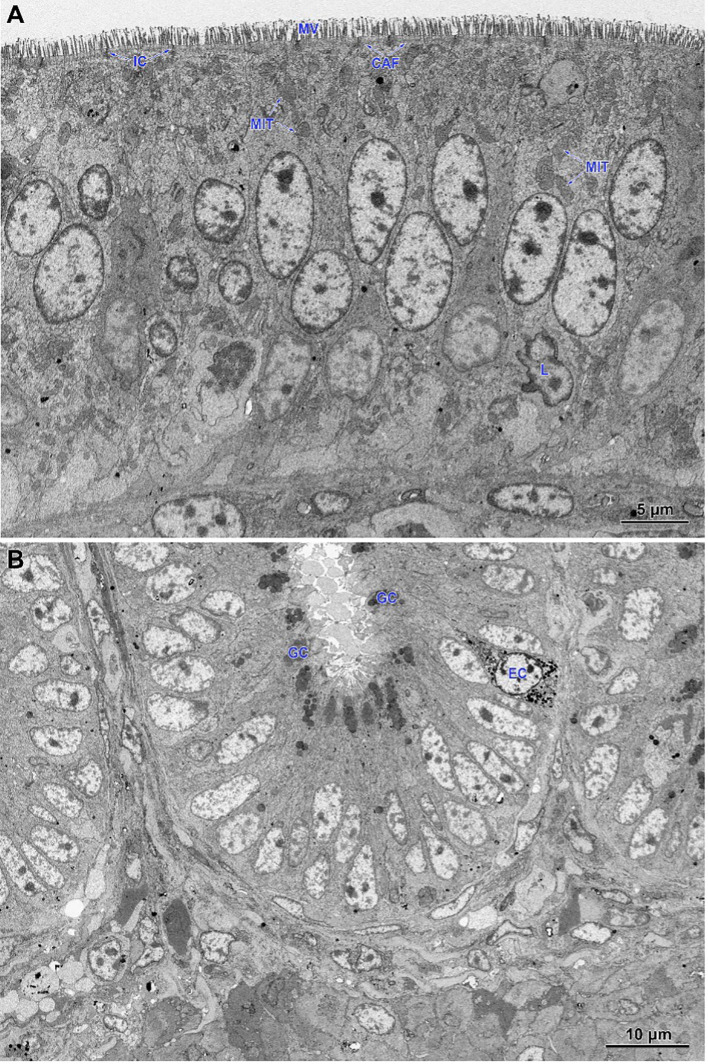

The electron microscopy study of the jejunum

In non-infected chickens (groups C and CBD + nano-Se), the epithelium of the villi consisted of a continuous and regular layer of columnar cells connected via tight and anchoring junctions located near their apical poles (f5). Microvilli covering enterocytes were regularly distributed but not very densely packed. The layer of cortical actin filaments was well-developed. The apical parts of enterocytes comprise mitochondria with a matrix of moderate electron density, Golgi apparatus and both forms of the endoplasmic reticulum. Lipid droplets were sparse in these cells. The goblet cells contained large secretory granules. Lymphocytes were sparse to moderate in number. The intestinal glands comprise immature enterocytes and goblet cells, as well as enteroendocrine cells (f5). Injured cells were extremely rarely found.